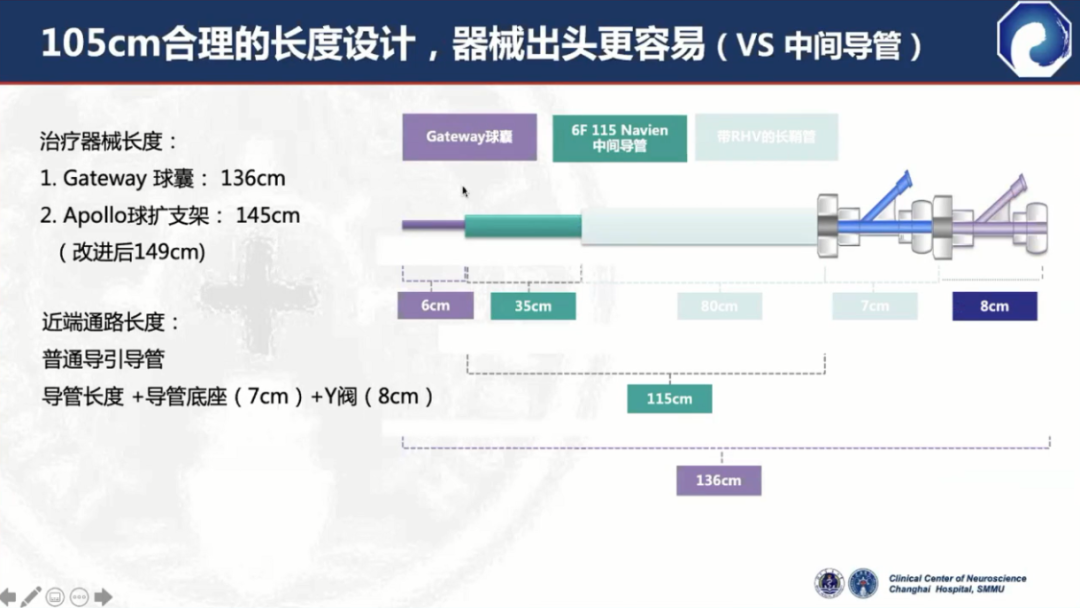

105cm长度设计,器械出头更容易